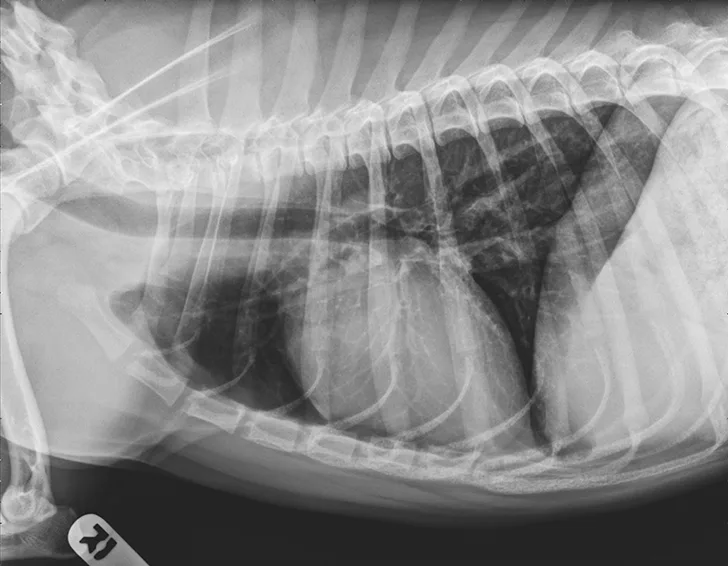

Thoracic radiographs showing a characteristic diffuse, patchy bronchointerstitial pattern (arrows)

Thoracic radiographs revealed a moderate, diffuse, bronchointerstitial pattern (Figure 1). The cardiac silhouette, pulmonary vasculature, and extrathoracic structures were normal. Airway sampling via bronchoscopy was recommended based on radiographic findings. CBC and serum chemistry profile were performed prior to sedation. Serum chemistry results were within normal limits. CBC revealed leukocytosis (24.3 x 103/µL; normal range, 4.9-17.6 x 103/µL) characterized by marked eosinophilia (10.4 x 103/µL; normal range, 0.07-1.49 x 103/µL), monocytosis (1.4 x 103/µL; normal range, 0.13-1.15 x 103/µL), and band neutrophilia (729/µL; normal range, 0-170/µL). Heartworm antigen test was negative.

Thoracic radiographs are generally characterized by a diffuse bronchointerstitial pattern with peribronchial cuffing and thickening of the bronchial walls. In some cases, bronchiectasis or alveolar infiltration may be observed.2,6-8 Occasionally, patchy pulmonary opacities create a nodular appearance.4 Radiography is critical for ruling out other common causes of cough and/or acute respiratory distress. Concurrent disease processes (eg, cardiomegaly, tracheal collapse) can complicate diagnosis.